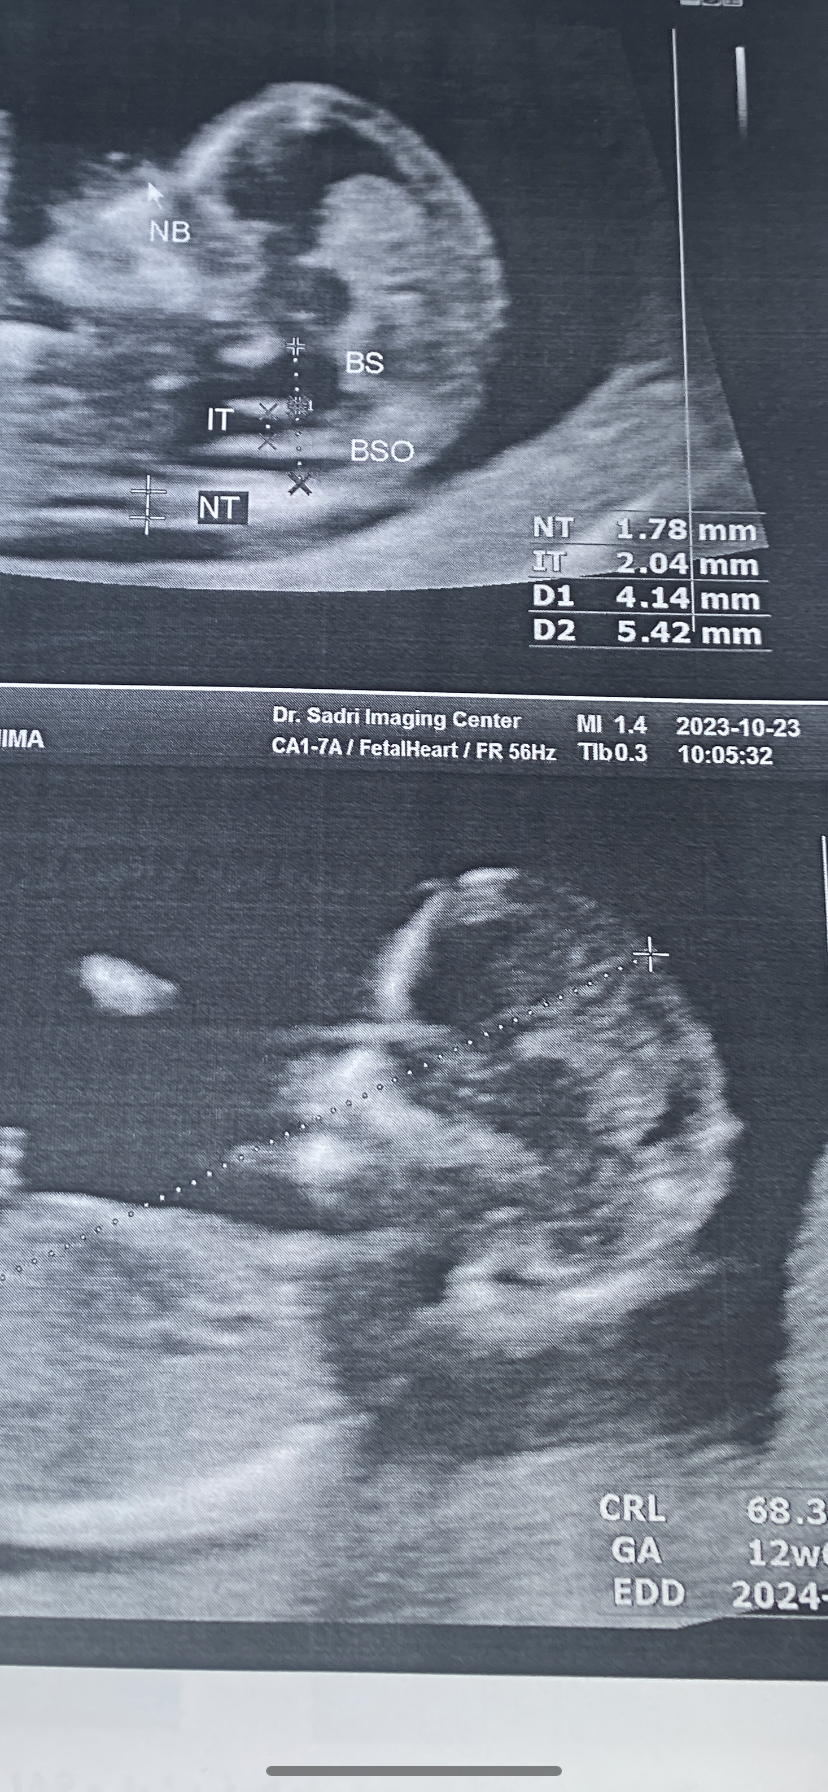

dokhtaretabeston7574 مدیر استارتر عضویت: 1402/01/24 تعداد پست: 1994 عنوان سونو ان تی 87 بازدید | 1 پست خانوما ان تی دخترم ازمایشش هنوز جوابش اماده نیساین ایتم ها به جز ان تی تو عکسش یعنی چی؟ 1402/08/04 | 13:54 0 نفر لایک کرده اند ... گزارش تاپیک نامناسب